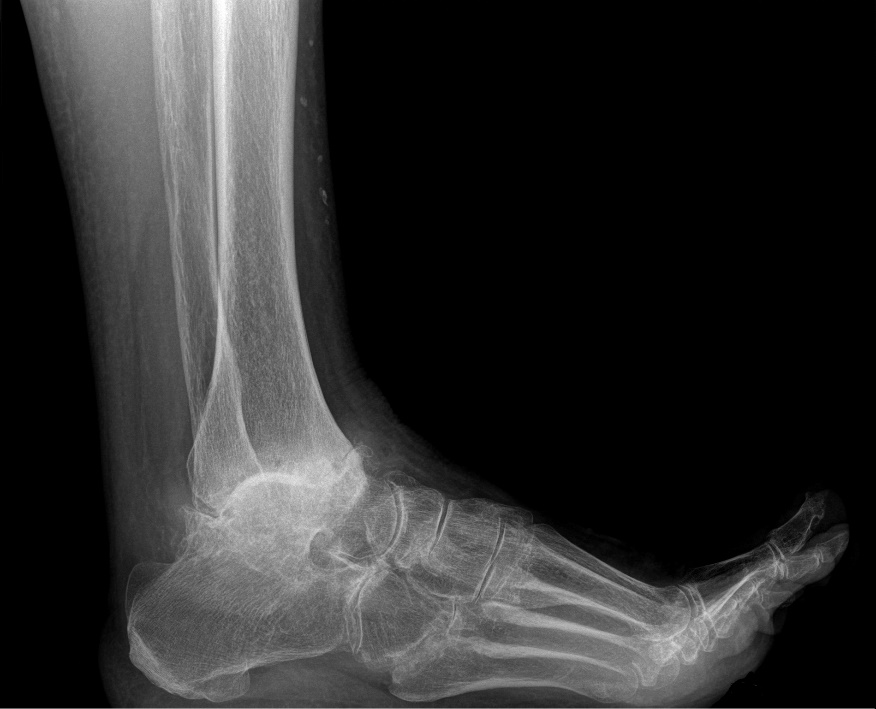

De diagnose artrose wordt reeds duidelijk na een klinisch onderzoek. De orthopedist analyseert het gangpatroon en onderzoekt de voet en de enkel. Bij vergevorderde artrose kan men de slijtage duidelijk zien op een staande radiografie. Bij een beginstadium kan een aanvullende arthro-CT van de enkel worden gemaakt. Hierbij wordt er een contrastvloeistof ingespoten in het enkelgewricht, waarna de CT-scan wordt gemaakt. Zo kan men beter zicht krijgen op de graad van slijtage en evt losse kraakbeen stukken.